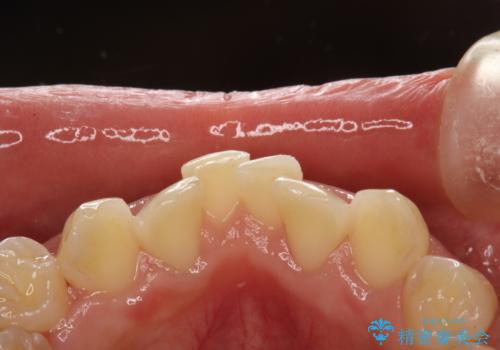

- 矯正治療前にステインを取りたいとのことで来院されました。ステインは前歯のみだったため、PMTC30分コースを行いました。

PMTCとは、歯科の専門家が器械を使用して行う歯のクリーニングのことです。普段の歯磨きでは取り切れない溝、キワなどの細かい部分も徹底的に除去します。ステインや歯石などが付着したままだと、虫歯や歯周病の発見がしずらいことがあります。特に矯正治療前には、念入りな虫歯や歯周病チェックが必要なため、PMTCでしっかりと汚れを除去しておくことが大切です。